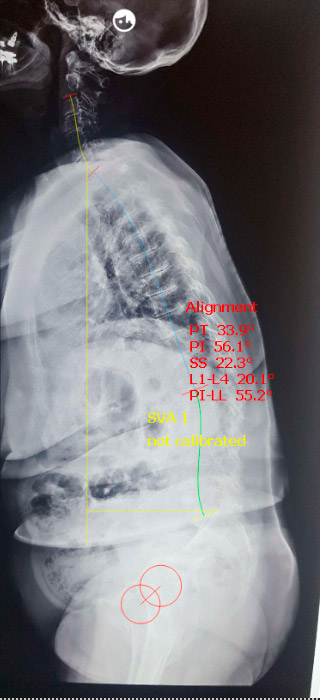

No plano sagital, observe que o alinhamento ultrapassa os 5cm do sacro, inclusive ultrapassa as cabeças femorais, demonstrando grave desequilibro sagital. Este tipo de desequilíbrio acarreta baixa qualidade de vida. (Fig. 3)

Fig. 3 – desalinhamento sagital

Utilizamos um programa computacional para estimar a correção, que deve neutralizar o balanço no plano sagital. Neste caso, aplicamos três osteotomias através de ALIF, estimando 1cm de abertura e 10 graus de lordose para cada segmento. Vejamos a correção estimada:

Fig. 5 – Pré-op